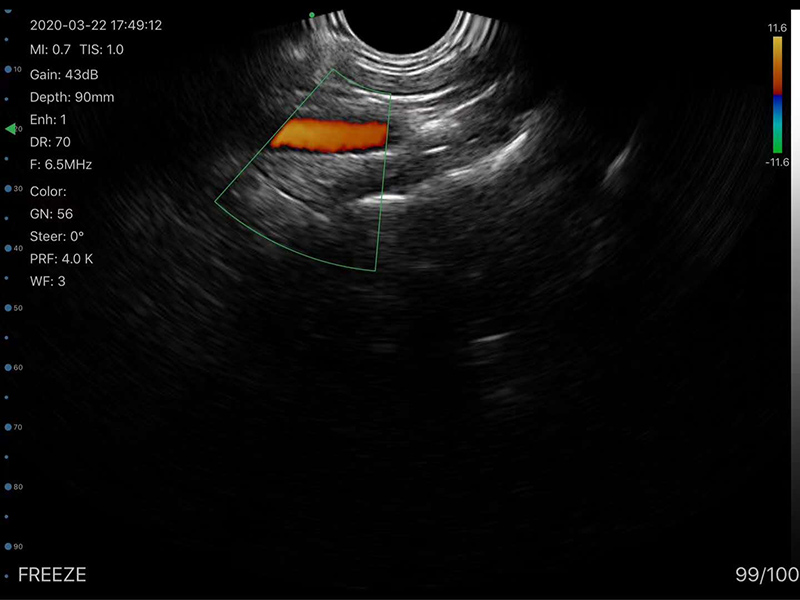

• Probe Head: R60 Convex+R13 Transvaginal

• Display mode: B, B/M, color doppler version with B+Color, B+PDI, B+PW

Transvaginal head 6MHz/8MHz, 30/60/90/120mm, R13